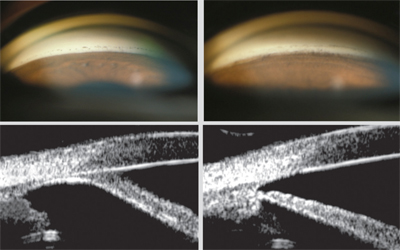

2. 전방천자 Anterior chamber paracentesis

전방천자는 각막에 직접 주사바늘을 찔러

전방에서부터 방수를 일부 빼내는 방법입니다.

전방내의 방수는 약 0.2 cc 정도되는데, 그중 0.05cc 즉 1/4 정도를 배출시킵니다.

각막천자이후 안압이 정상화고, 각막 부종이 회복되면,

레이저 시술을 시행할 수 있습니다.